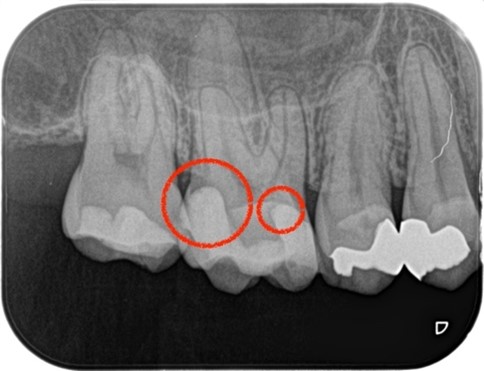

_術前のレントゲン画像、虫歯処置の箇所マーク|目白マリア歯科.jpg)

_術前のレントゲン画像|目白マリア歯科.jpg)